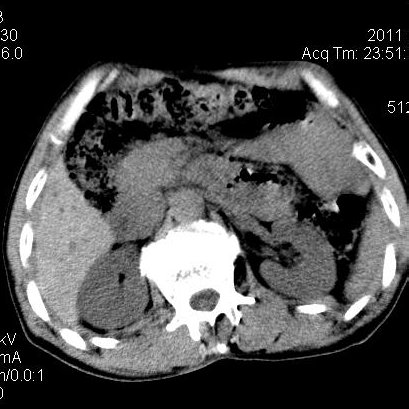

肝左叶发育异常

男性,55岁,骑摩托车摔倒后入院,自述右上腹疼痛

[backcolor=#FF0000]第一次诊断的时候也是这么肯定,可是床旁超声检查并没有发现明显异常,而且患者的一般症状都良好。还好临床只是保守治疗,没有立即手术,第二次复查的时候没有一点变化,又做了MRI检查,没有血肿,

这是一例肝左叶发育异常的,很个性吧~[/backcolor]